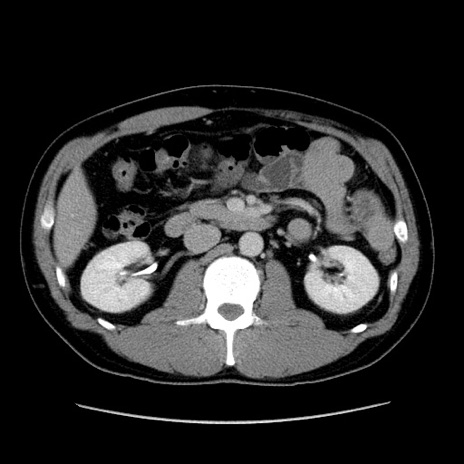

冠状断像

【症例】30歳代男性

【主訴】腹痛、嘔吐

【現病歴】昨晩から突然の腹痛あり、その後嘔吐、軟便も出現。腹痛が改善しないため救急搬送となる。2日前にしめ鯖の食事歴あり。

【身体所見】意識清明、苦悶様、BP 135/90mmHg、BT 35.7℃、腹部:平坦、やや硬、心窩部〜臍部に自発痛、圧痛あり、筋性防御+、反跳痛-

【データ】WBC 8100、CRP 0.57